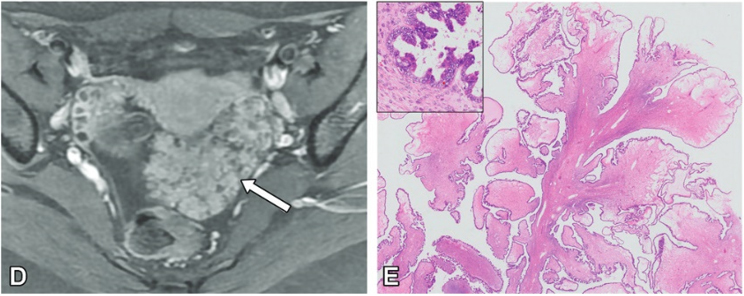

【病理所見】

• HE ルーペ像

• HE(x20) Stalk 部分拡張血管や dense な線維性結合組織成分を認める

• HE(x40) 辺縁部分 ①浮腫状間質を取り囲み、腫瘍細胞が低乳頭状に増殖する。 矢印:腹腔内に粘液が漏出

• HE(x100) 辺縁部分 ② 細胞質内粘液を有する内頸部型の粘液円柱上皮が低乳頭状に増殖。

矢印:上皮下には内膜間質様の細胞密度の高い間質を認め、間質浸潤はない。

診断:漿液粘液性境界悪性腫瘍

seromucinous borderline tumor: SMBT